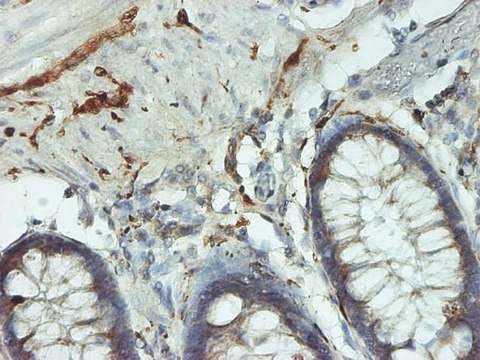

ELISA (i), IHC (p), WB

immunohistochemistry (formalin-fixed, paraffin-embedded sections): suitable, indirect ELISA: suitable, western blot: 1-5 μg/mL

The protein encoded by this gene belongs to the peptidase C12 family. This enzyme is a thiol protease that hydrolyzes a peptide bond at the C-terminal glycine of ubiquitin. This gene is specifically expressed in the neurons and in cells of the diffuse neuroendocrine system. Mutations in this gene may be associated with Parkinson disease

Ubiquitin C-terminal hydrolase L1 (UCHL1) is encoded by the gene mapped to human chromosome 4p14. The encoded protein is a deubiquitinase, which is part of the ubiquitin proteasome system (UPS). UCHL1 is specifically expressed in the nervous system and gonads.

Ubiquitin C-terminal hydrolase L1 (UCHL1) catalyzes the hydrolysis of carboxy-terminal ubiquitin esters and amides. It plays an essential role in epithelial-mesenchymal transition. In addition, UCHL1 is also implicated in the cell invasion and in the cell cycle regulation. UCHL1 gene acts as an oncogene in various types of cancers including glioma, gastric cardiac adenocarcinoma (GCA) and colorectal cancer. It also acts as a susceptibility gene for Parkinson′s disease.